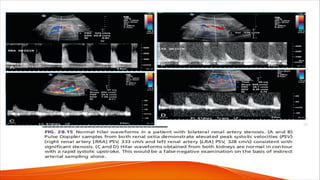

Normal Renal Doppler waveform

• The normal peak systolic velocity (PSV) in

the renal arteries ranges from 74 to 127

cm/s in both adults and children.

• Children tend to have slightly higher

velocities than adults.

• The kidneys are end organs that require

continuous forward flow throughout both

systole and diastole, therefore the renal

arteries demonstrate a low resistance

waveform pattern with a rapid systolic

upstroke and persistent forward flow in

diastole

• An early systolic compliance peak or notch

may be seen in some patients.